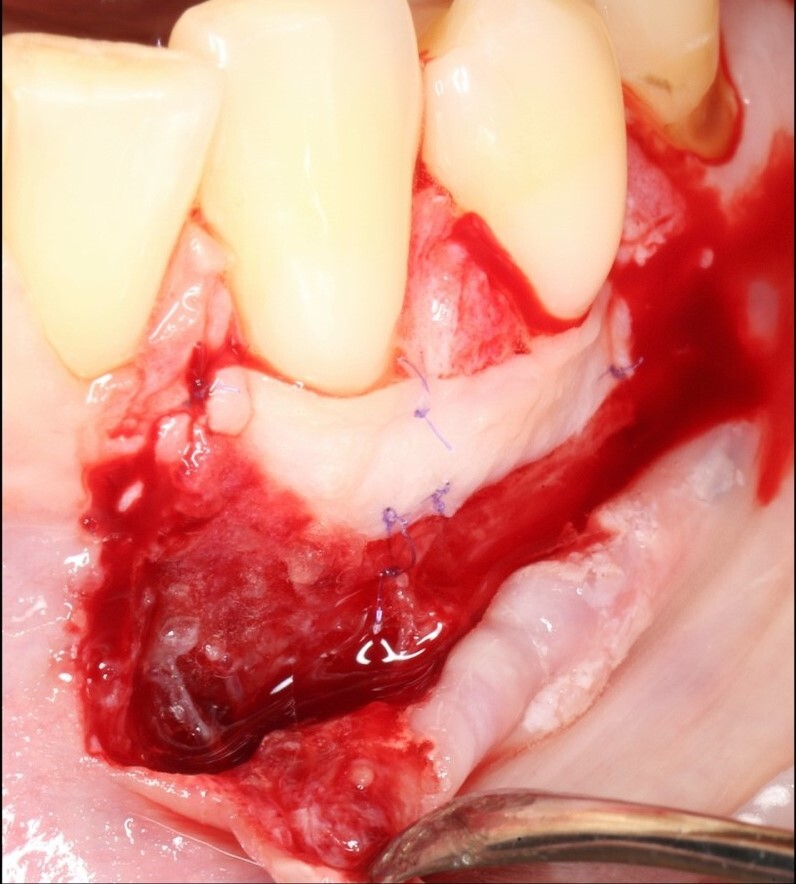

Устранение эстетических осложнений в области имплантатов. Преимущества методики VISTA

Лекция посвящена современным подходам к коррекции эстетических недостатков в области мягких тканей вокруг зубных имплантатов. Будет рассмотрена методика VISTA (Vertical Incision Subperiosteal Tunnel Access), как минимально инвазивный способ работы с мягкими тканями. Обсудим ключевые преимущества: снижение травматичности, высокую предсказуемость результатов и улучшение эстетики в зонах улыбки. Особое внимание уделим выбору донорских материалов, работе с сосудистой сетью и нюансам заживления. Лекция будет сопровождаться клиническими примерами и практическими рекомендациями для применения метода в повседневной практике.